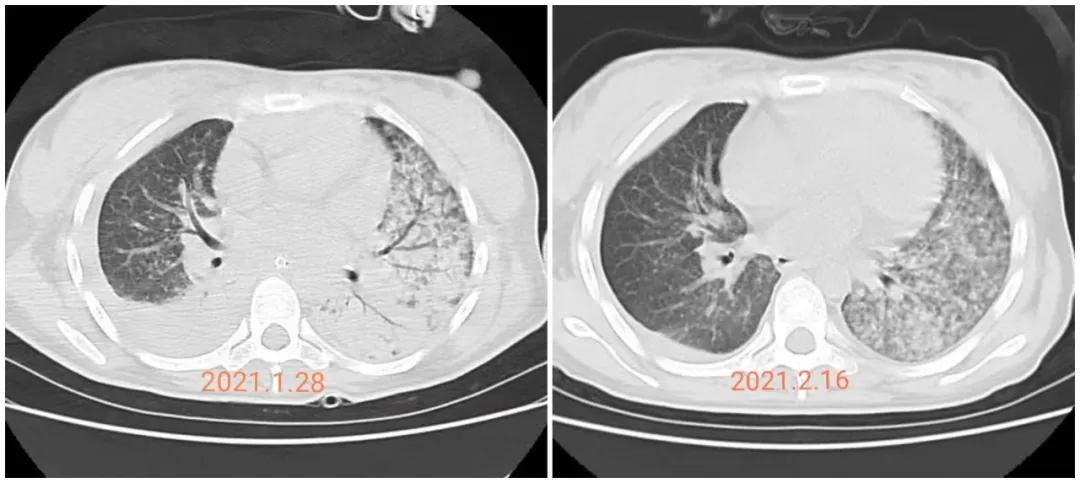

經(jīng)過(guò)醫(yī)護(hù)團(tuán)隊(duì)的共同努力,患者于2021年2月2日成功拔除氣管插管,改予無(wú)創(chuàng)呼吸機(jī)輔助通氣治療,于2021年2月4日復(fù)查胸部CT見(jiàn)雙肺病灶較前明顯吸收改善,患者病情逐漸恢復(fù),逐漸拔除胃管及尿管、中心靜脈置管,于2021年2月8日轉(zhuǎn)入ICU康復(fù)病房繼續(xù)治療,于2021年2月19日好轉(zhuǎn)出院。